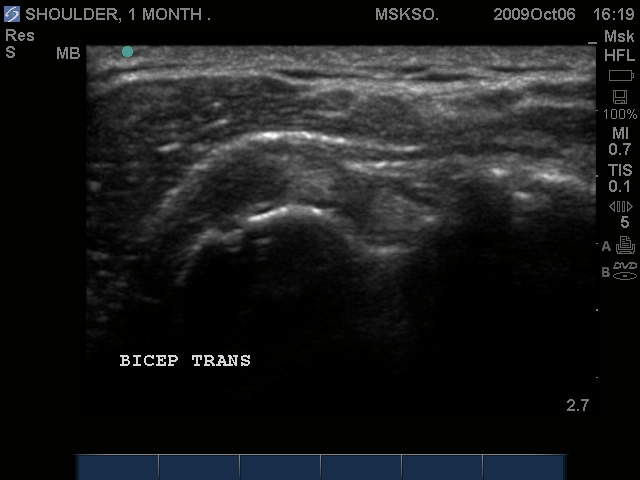

Subluxing Bicep tendon over lesser tuberosity

Subluxing Bicep tendon over proximal lesser tuberosity

Splitting Bicep tendon over lesser tuberosity